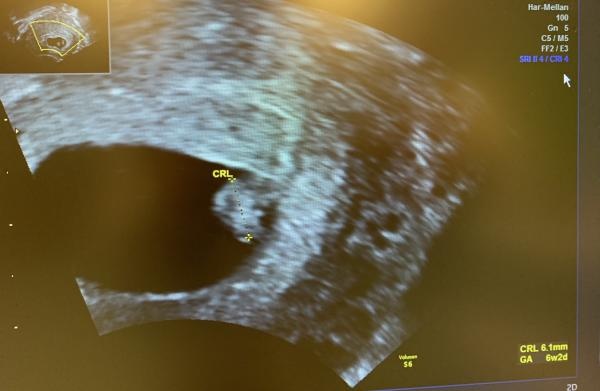

Ja, var hos min läkare den 12:e och hon såg inget nytt, inget foster så hon sa att jag skulle komma tillbaka den 16:e (imorgon) igen. Men jag har haft ont i ena sidan magen, typ i ljumsken i flera dagar i kombination med spottings och och igår blev det värre så jag ringde till SÖS och dom tyckte jag skulle komma in till gynakuten. Gissa vad jag fick se efter 7 timmars väntetid: Ett perfekt litet tickande hjärta och ett foster på 6,1 mm och låg jättebra till i livmodern. Det såg jättefint ut sa hon! <3 Hon fattade inte alls hur min läkare kunde säga 2 dagar innan att det inte fanns nånting där för så mycket kan inte hända på två dagar.